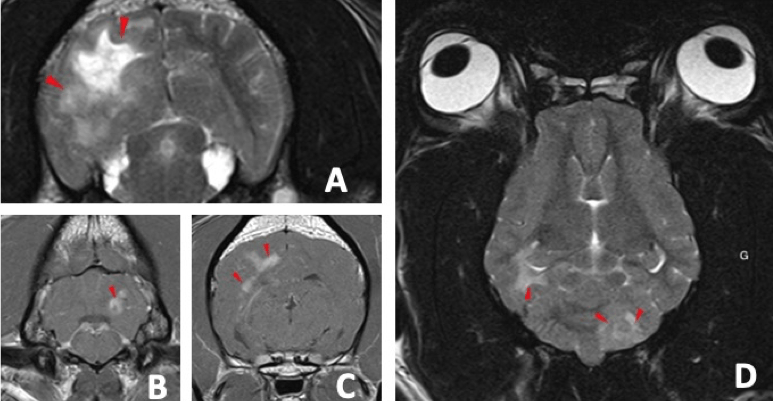

À propos des méningoencéphalomyélites canines

1/ Les méningoencéphalites chez le chien sont secondaires à des causes infectieuses le plus fréquemment en France ? Réponse : Faux Le terme méningoencéphalomyélite indique une inflammation du système méningé (méningo-), de l’encéphale (encéphalo-) et de la moelle épinière (myél-). Cette inflammation peut être secondaire à un processus infectieux ou auto-immun. Les… Lire la suite